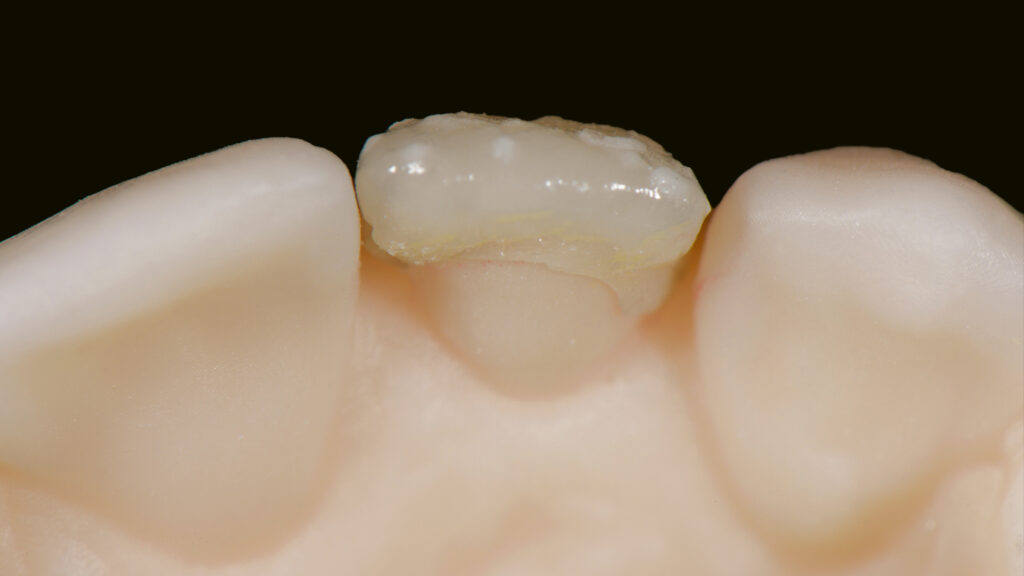

Nach dem zweiten Brand wird die Form kontrolliert, um dann auf dem ungesägten Modell die Kontaktflächen und die Ausbildung der Leisten zu überprüfen (Abb. 30 und 31). Die labialen und distalen Leisten definieren die Dimension und die Grundform des Zahnes (Abb. 32). Abschließend wird das Veneer fertiggestellt; es erfolgt ein Glanzbrand (Abb. 33). Die Feinabstimmung des Glanzgrades bei Einzelkronen ist ebenso wichtig wie alle anderen Parameter (z. B. Helligkeit, Sättigung, Farbe). Um einen matten Glanz zu erzielen, wird in diesem Fall eine kürzere Haltezeit von 30 Sekunden und eine niedrigere Endtemperatur von 745°C gewählt. Ein zu hoher Glanzgrad würde den künstlichen Zahn „verraten“. Die Oberflächenstruktur ist patientenspezifisch. In die Zahnoberfläche werden Perkymatien – feine horizontale Wachstumsrillen – eingearbeitet, die mit den Jahresringen eines Baumes vergleichbar sind. Es ist wichtig, die Oberflächentextur dem Restgebiss anzupassen. Auf der Oberfläche entstehen durch die Lichtstreuung der Mikrostruktur bestimmte Lichtreflexe (Abb. 34). Die Natur macht es vor: Durch die Beschichtung der keramischen Restauration mit Goldpulver werden die natürlichen Makro- und Mikrostrukturen deutlich sichtbar (Abb. 35). Zudem macht eine „polar_eyes“-Aufnahme (Kreuzpolfilter) die keramische Schichtung im Zahninneren sichtbar (Abb. 36). Die Aufnahme zeigt die natürliche Fluoreszenz und insbesondere die mit „Smoky White” erzielte Imitation der Kalkflecken (Abb. 37). Dem Einsetzen des Keramikveneers 22 schließt sich die implantologische Therapie regio 12 an.

Die individuelle Formgebung der ASC-Implantatkronen ermöglicht einen reizfreien Schleimhautkontakt mit Titanadapter und konischer Innenverbindung zum Implantat (Abb. 56 und 57). Die keramische Verblendung des Zirkonoxid-Abutments erfolgt analog und ebenso detailgetreu wie beim keramischen Veneer und mit der gleichen Verblendkeramik (Lumex AC). Nach der Verblendung wird die Implantatkrone auf dem Meistermodell verschraubt und eine letzte Kontrolle der Kontaktflächen (Abb. 58 und 59), der Artikulation, der seitlichen Bewegungen und der Eckzahnführung durchgeführt. Abbildung 60 zeigt den nahtlosen Übergang der Implantatkrone zur natürlichen Gingiva. Eine Überkonturierung könnte zu einer apikalen Verschiebung führen. Eine polar_eyes-Aufnahme macht das Innere der Krone und die Details besser sichtbar (Abb. 61).

Ergebnis ist eine ästhetisch hochwertig verblendete Implantatkrone auf einem individuellen Zirkonoxidgerüst mit Titanadapter. Die mesiale Ansicht zeigt das Emergenzprofil und eine vertikale Achsneigung, die quasi von inzisal zur Implantatmitte verläuft. Der subgingivale Anteil tritt schlank aus dem Implantat aus und unterstützt mit einem konvexen Übergang zur Implantatkrone das Niveau der Gingiva (Abb. 62). Die Abutmentbasis aus Titan sorgt für eine präzise Passung, die gut kontrollierbar ist. Abbildung 63 zeigt die verschiedenen Komponenten der Implantatrestauration: Titanadapter, eine Omnigrip-Schraube und Omnigrip-Schraubendreher sowie die Vollkeramikkrone.